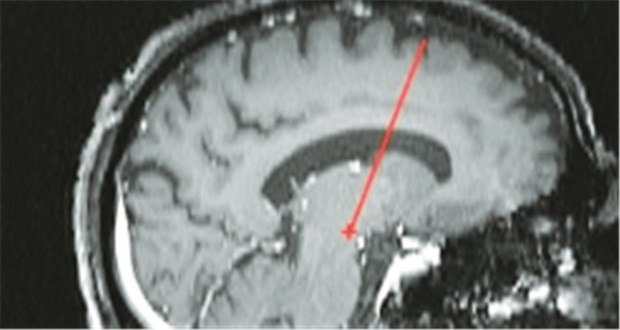

MRT-kontrollierte Implantation von THS-Elektroden.

© Foto: Professor Volker Sturm